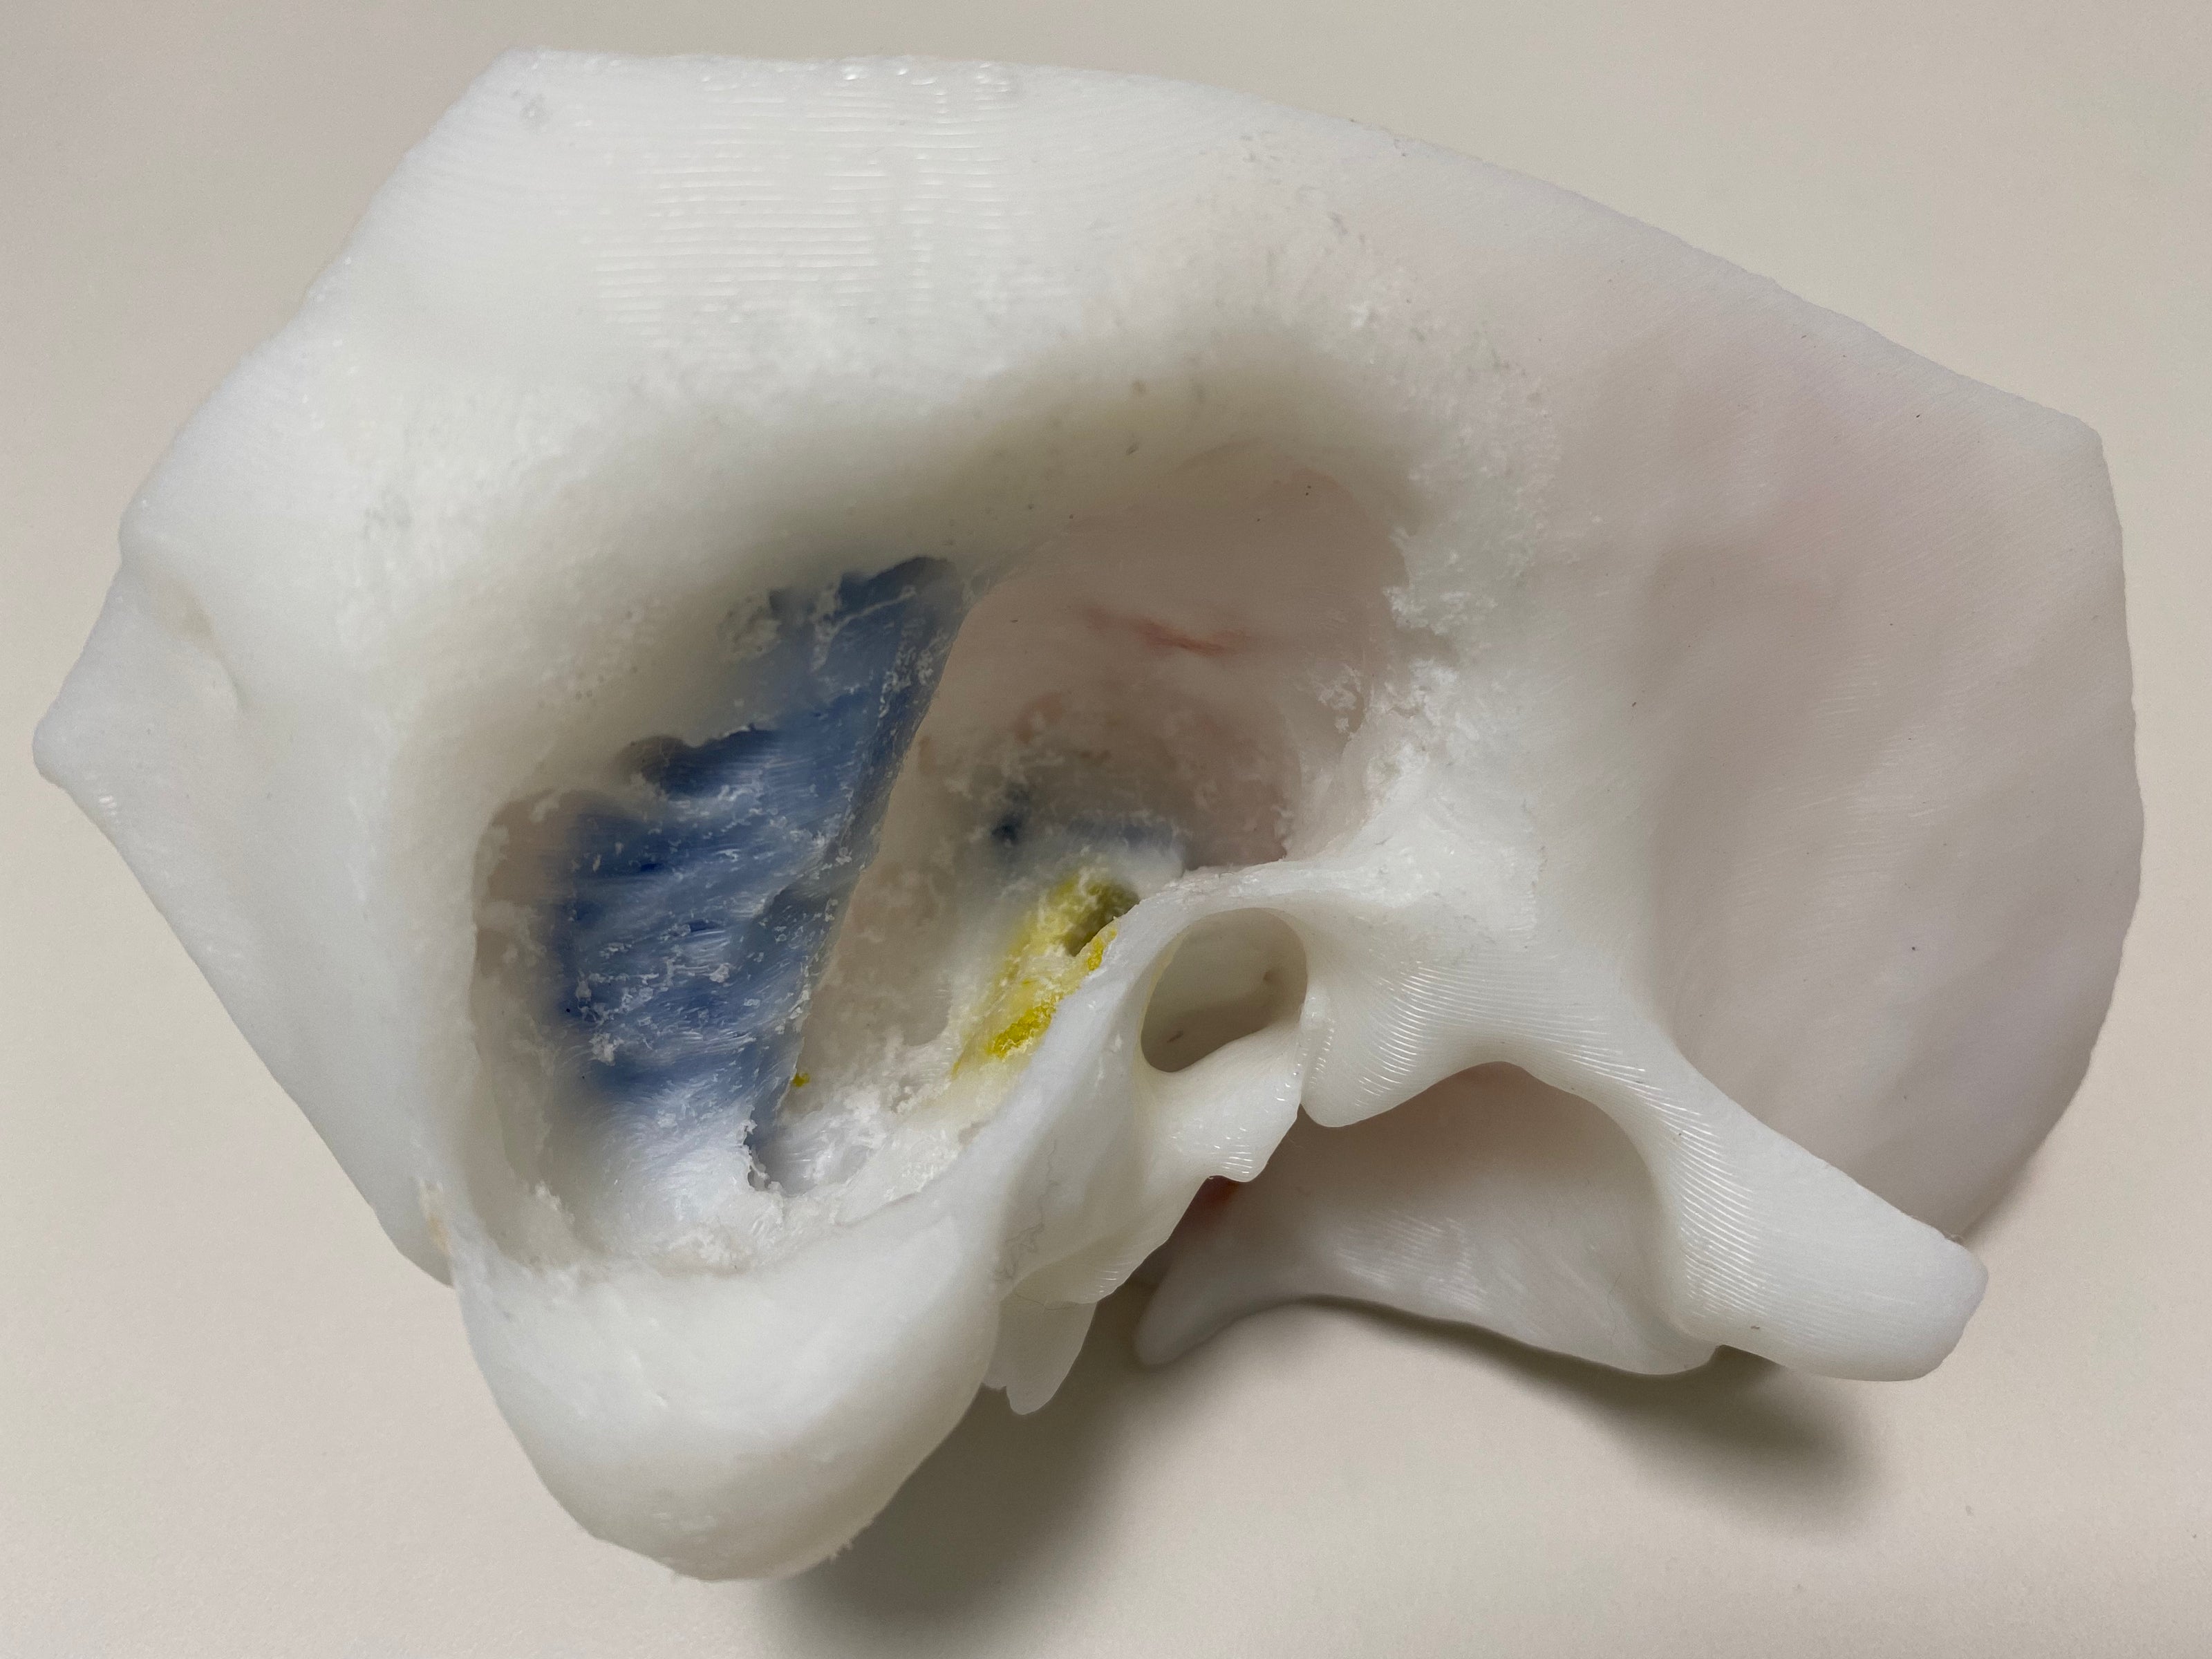

Dissect each one to learn human temporal bone anatomy, hearing and vestibular systems.

*High Contrast Colors* 3D Temporal Bones to Introduce Anatomy (6-pack)

Regular price $402.00 USDRegular priceUnit price per -